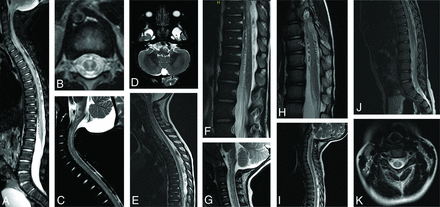

Spinal MR imaging results for each patient are detailed in the Online Supplement Data and are highlighted in Fig 1. On T2-weighted images, abnormally ectatic and tortuous pial blood vessels surrounded the spinal cord and conus medullaris. There was abnormal T2 signal hyperintensity in the central spinal cord (anterior > posterior) and cord tumefaction in all patients. T2 signal hyperintensity longitudinally involved the entire cord and extended into the ventral medulla. Variable cord parenchymal enhancement was present in 2 patients.

Spine MR imaging findings. A, Midline T2-weighted sagittal MR image of the spine in patient 1 shows abnormal T2-weighted hyperintense signal in the thoracic spinal cord and conus medullaris. Spinal cord volume expansion is also present. There is conspicuous abnormal perimedullary vascular ectasia anterior to the conus medullaris and thoracic spinal cord. B, Axial T2-weighted image of the midthoracic spine shows the distribution of abnormal T2-weighted signal hyperintensity within the central and anterior spinal cord. C, Midline T2-weighted sagittal MR image of the cervical spine reveals abnormal T2-weighted hyperintense signal in the central cervical spinal cord and ventral medulla. There is diffuse spinal cord swelling affecting the region of the cervical enlargement. D, Axial T2-weighted image of the brain at the level of the medulla shows T2-signal hyperintensity in the pyramids, more conspicuous on the left. E, Midline T2-weighted sagittal MR image of the cervical and thoracic spine in patient 4 shows abnormal T2-weighted hyperintense signal in the ventral cervical and thoracic spinal cord and medulla. There is spinal cord volume expansion, prominent in the region of the cervical enlargement, and abnormal perimedullary vascular ectasia anterior to the thoracic spinal cord. F, Midline T2-weighted sagittal MR image of the lower thoracic and lumbar spine reveals abnormal T2-weighted hyperintense signal in the anterior spinal cord. There is diffuse spinal cord swelling, severely affecting the region of the lumbar enlargement. Note marked ectasia of the perimedullary vessels anterior to the spinal cord. G, Midline T2-weighted sagittal MR image of the cervical spine in patient 3 shows abnormal T2-weighted hyperintense signal in the central and anterior cervical spinal cord as well as in the ventral medulla. Mild expansion of cervical spinal cord volume is also present. Conspicuous abnormal perimedullary vascular ectasia anterior to the cervical spinal cord is demonstrated. H, Midline T2-weighted sagittal MR image of the lower thoracic spine reveals abnormal T2-weighted hyperintense signal in the central and anterior thoracic spinal cord and conus medullaris, with mild associated volume expansion. Note marked perimedullary vascular ectasia surrounding the spinal cord. I, Midline T2-weighted sagittal MR image of the cervical and thoracic spine in patient 2 shows abnormal T2-weighted hyperintense signal in the cervical and thoracic spinal cord. The region of the cervical enlargement is severely affected and shows mild volume expansion. J, Midline T2-weighted sagittal image of the lower thoracic and lumbar spine shows abnormal T2-weighted signal hyperintensity within the anterior spinal cord. There is conspicuous perimedullary vascular ectasia anterior to the conus medullaris. K, Axial T2-weighted MR image of the cervical spine reveals abnormal T2-weighted hyperintense signal in the central cervical spinal cord.